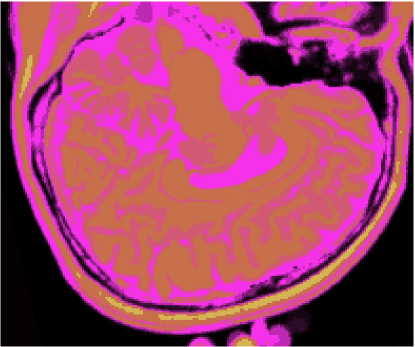

Os gráficos das figuras 14, 15, 16 e 17 mostram os resultados das medidas dos índices de fidelidade ϵMEsubscriptitalic-ϵME\epsilon_{\textnormal{ME}}, ϵMAEsubscriptitalic-ϵMAE\epsilon_{\textnormal{MAE}}, ϵRMSEsubscriptitalic-ϵRMSE\epsilon_{\textnormal{RMSE}} e ϵPSNRsubscriptitalic-ϵPSNR\epsilon_{\textnormal{PSNR}}, enquanto os gráficos das figuras 18 e 19 exibem os resultados do erro de quantização, Jesubscript𝐽𝑒J_{e}, e do índice de Omran, Josubscript𝐽𝑜J_{o}, para os métodos KO, CM, KM, IC-CAN, EQ-CAN, IC-PME e EQ-PME, em função dos níveis percentuais de ruído, para os 6 volumes de 181 fatias de 3 bandas. A figura 20 mostra os resultados de classificação, enquanto a figura 21 exibe os resultados de quantização para a imagem sem ruído da fatia 97, figura 5, usando os métodos IC-CAN-KM, IC-PME-KM, EQ-CAN-KM e EQ-PME-KM. É possível perceber a partir das imagens que a introdução da otimização dialética permitiu ao k-médias identificar diferentes classes dentro do fundo da imagem.

Entretanto, o gráfico da figura 18 ilustra que, embora os resultados de 0% a 1% de ruído mostrem que os resultados não são distinguíveis entre si quanto ao erro de quantização, a partir de 1% de ruído os valores do erro de quantização para o método EQ-PME são bem menores do que as medidas de erro de quantização para os outros métodos, mostrando que a otimização do mapa de k-médias usando o método dialético com entropia maximizada em função do erro de quantização tem resultados qualitativamente superiores àqueles obtidos com os outros métodos, conforme também a figura 21.

No entanto, da figura 18 também fica claro que, embora todos os métodos baseados na otimização pelo método dialético retornem medidas de Josubscript𝐽𝑜J_{o} muito melhores que aquelas obtidas usando KO, CM e KM, o método EQ-PME é o que apresenta o melhor resultado dentre todos, destacando-se dos outros métodos a partir de 1% de ruído percentual, ou seja: o método baseado no mapa de k-médias otimizado usando o método dialético de entropia maximizada em função do erro de quantização Jesubscript𝐽𝑒J_{e}. Esse resultado não deixa de ser interessante e curioso, pois mostra que o índice de Omran Josubscript𝐽𝑜J_{o}, no caso das imagens utilizadas, é dominado pelo erro de quantização Jesubscript𝐽𝑒J_{e}, dado que a otimização em função do índice de Omran usando os métodos dialéticos canônico (IC-CAN) e com entropia maximizada (IC-PME) são idênticos e qualitativamente inferiores, assim como os resultados obtidos usando o método dialético canônico em função de Jesubscript𝐽𝑒J_{e} (EQ-CAN). Isso também indica que a aplicação do Princípio da Máxima Entropia diferenciou sensivelmente o algoritmo de sua versão canônica, tendo acelerado a convergência para a otimização em função do erro de quantização, como bem atestam os resultados.

Esses resultados, combinados àqueles apresentados anteriormente, mostram que, para a aplicação ilustrada neste trabalho, o método EQ-CAN foi superior aos outros métodos de classificação não supervisionada e quantização apresentados, tanto quando são utilizados índices de fidelidade quanto índices de validade do agrupamento, o que mostra que, para as imagens utilizadas, tanto existe um predomínio do erro de quantização Jesubscript𝐽𝑒J_{e} sobre o índice combinado de Omran Josubscript𝐽𝑜J_{o} (onde este último, por sua vez, contém o primeiro conforme expressões 58 e 52), quanto existe uma forte influência da aplicação do Princípio da Máxima Entropia ao método dialético de busca e otimização, que nesta aplicação ajudou o método a ter sua convergência acelerada ou até mesmo a vencer um mínimo local.

Refer to caption

(a)

(b)

(c)

(d)